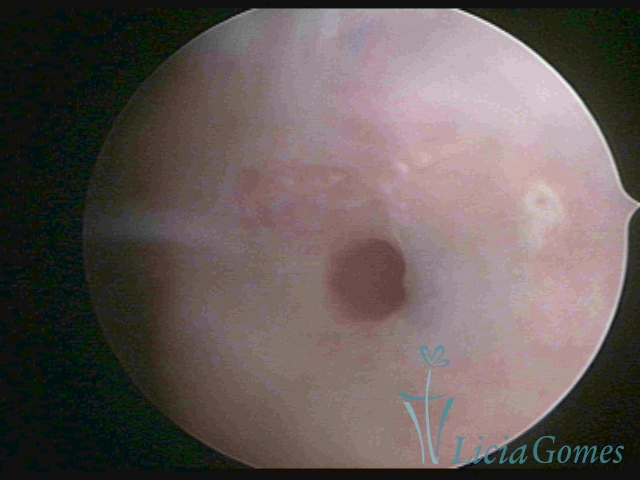

Terceira porção ou porção superior

Apresenta a mucosa com a superfície lisa e pouco vascularizada até a altura do orifício interno